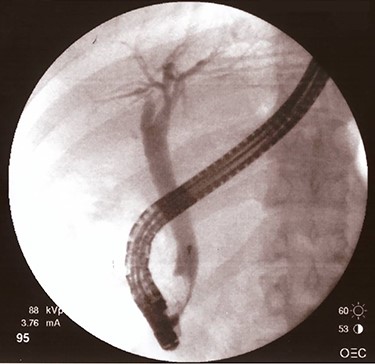

The patient and his parents disagreed to perform firstly a computered tomography scan, and then an magnetic resonance cholangiopancreatography. Unusually, they agreed about endoscopic retrograde cholangiopancreatography (ERCP), so it was performed and cholangiography showed an ab-extrinsic stricture of CBD caused by a compression from a biliary stone in the infundibulum of the gallbladder; the upper biliary duct was dilated with various defects as biliary sludge and stones (Fig. 1A). Moreover, late opacification of gallbladder showed lithiasis and, more important, an unexpected opacification of the right colonic lumen (Fig. 1B). MS with both cholecystobiliary (due to the erosion of the wall of the CBD that involves up to two-thirds of its circumference) and cholecystocolonic fistula without gallstone ileum was diagnosed and classified as type III according to Csendes et al. [4] and type V according to Beltran et al. [5]. A partial toilette of CBD was undergone, arranging a drainage with a biliary ‘pigtail’ prob, but the surgical treatment was immediately undergone due to the evidence of fluid faecaloid-like aspiration through the biliary drainage.

Cholangiography first ERCP. (A) Ab extrinsic compression of CBD; (B) tardive opacization of gallbladder showing fistula with colon.